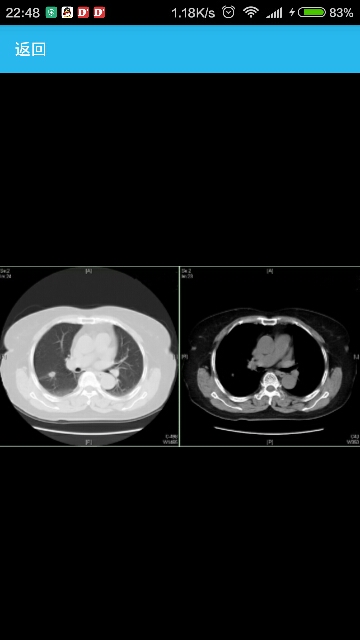

患者女性,62岁,主因“查体发现肺部占位1周”入院。 病史患者于1周前行常规健康检查时胸部CT提示右肺上叶占位,患者无咳嗽咳痰,无发热,无咳血,无胸闷胸痛,无周身乏力。为行进一步诊治就诊我科。既往高血压病3年,现口服药物治疗,血压水平140/90mmHg。吸烟30年,0.5包/日。 临床表现一般情况可,胸廓无畸形,无杵状指。胸壁静脉无曲张,胸骨无压痛。肺部呼吸运动度对称,无胸膜摩擦感,无皮下捻发感,左肺叩诊清音,肺底移动度正常。呼吸规整,左肺上部呼吸音较粗,未闻及干湿啰音右肺呼吸音清,右肺未闻及干湿啰音。双侧锁骨上未扪及肿大淋巴结。 辅助检查实验室检查:血常规:白细胞(WBC):12.69×109/L↑,血红蛋白(HGB):106.00g/L↓,血小板(PLT) 202.00×109/L;生化:谷丙转氨酶(ALT) 14.6U/L,谷草转氨酶(AST) 15.2U/L,碱性磷酸酶(ALP) 84.5U/L,总胆红素(TBIL) 12.70umol/L,直接胆红素(DBIL) 4.12umol/L,肌酐(血)(Cre) 41.5umol/L↓;肿瘤标记物:鳞状细胞癌抗原(SCCAg) 0.6ng/mL,癌胚胎抗原(CEA) 2.88ng/mL,细胞角质蛋白19片段(CYFRA21-1) 0.74,癌抗原CA-125(CA-125) 7.5U/mL,神经元特异性烯醇化酶(NSE) 13.76ug/L; 影像学检查:胸片正侧位:双肺纹理清晰,右肺中野见类圆形致密影,边界欠清,边缘多发毛刺,大小约1.3cm×1.5cm。气管居中,右肺门影略致密。纵隔不宽,心影形态大小未见异常,双膈面光滑,肋膈角锐利。胸部CT(平扫+增强):肺窗:两肺容积正常,肺纹理略增多,右肺上叶后段见类圆形结节影,大小约14x10x10mm,边缘见毛刺,临近胸膜受牵拉。纵隔窗:右侧肺门见多发淋巴结,最大者大小约14x11mm。 诊断肺癌、高血压病;依据:老年女性,吸烟15包/年, 胸片和胸部CT提示明显肺癌征象。 治疗患者分期为T2aN0M0,IB期。此期患者进行术后辅助化疗的证据尚不充分,根据第七版NCCN治疗指南,IB期患者如具备肺癌复发的高危因素(低分化、脉管内癌栓、腺癌患者CEA升高、亚肺叶切除或淋巴结清扫不彻底),应进行术后的辅助化疗。此患者不具备任何一项高危因素,可不行术后化疗。